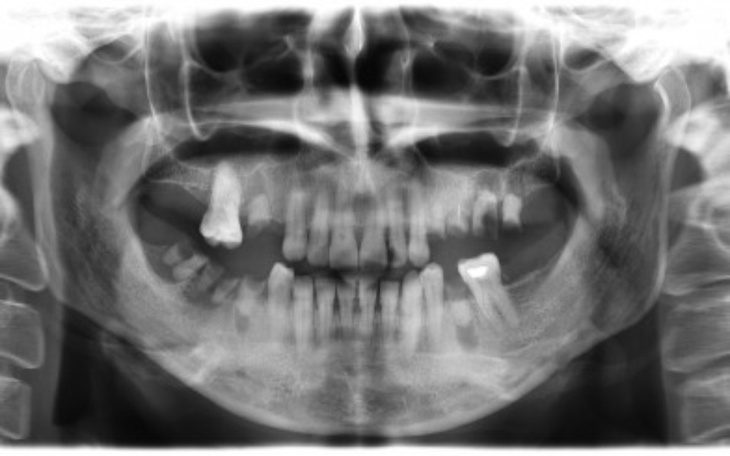

Mam na imię Natalia i mam 20lat. Od dziecka jestem chorowitą osobą. Rok temu stwierdzono u mnie paradontozę, gdzie na skutek choroby wypadło mi aż 6 zębów.

"Paradontoza to choroba tkanek przyzębia, której skutkiem może być utrata zębów. Terminem tym określa się wszelkie przewlekłe procesy zapalne dziąseł i głębiej znajdujących się tkanek."

Stomatolog powiedział, że w przeciągu 1,5 roku wypadną mi kolejne zęby. Dlatego proszę Was bardzo o pomoc. Zbieram na implanty, żeby móc się cieszyć pięknym uśmiechem.